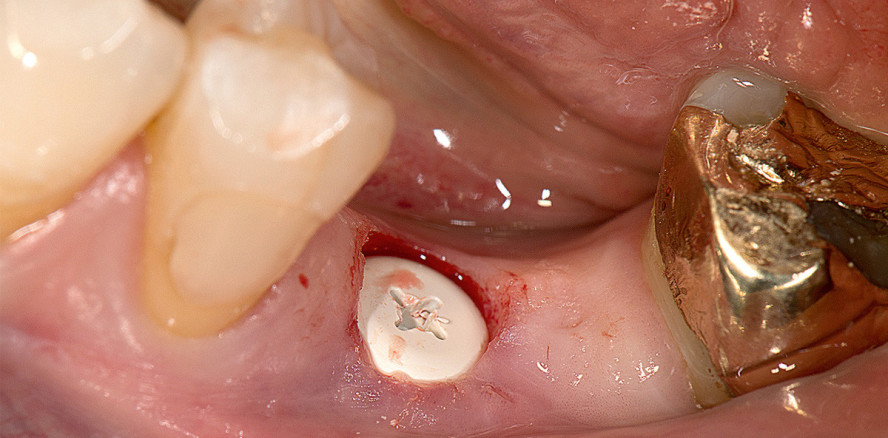

Bei einer 49-jährigen, systemisch gesunden, nicht rauchenden Patientin wurde sechs Monate zuvor der Zahn 36 extrahiert (Abb. 1). Indikationen waren eine rezidivierende periapikale Entzündung und Schmerzen. Die Patientin wünscht eine vollständig metallfreie Versorgung, einschließlich Ersatz der vorhandenen insuffizienten Goldrestaurationen. Der Kieferkamm einschließlich Weichgewebe ist aufgrund der klinischen und radiologischen Befunde für eine Implantation ohne Augmentation ausreichend dimensioniert.

Nach Stanzen der Schleimhaut (Abb. 3) wird das Implantatlager wie gewohnt aufbereitet (Abb. 4). Vor der Implantation wird Cephalosporin-Pulver (Cefaclor) mit einem Applikator in das Implantatbett gebracht.

Im nächsten Schritt wird ein Zirkoniumdioxidimplantat (Zeramex XT, Dentalpoint) mit dem zugehörigen Pick-up eingeschraubt (Abb. 5 und 6). Die vier kreuzförmig angeordneten retentiven Elemente sorgen für ein ideales Übertragungsmoment, Spannungsspitzen im Knochen werden vermieden. Nach dem Einschrauben (35 Ncm; Abb. 7) wird die PEEK-Heilkappe mit antibiotischer Heilsalbe (Solcoseryl, MEDA Pharma) abgedeckt.